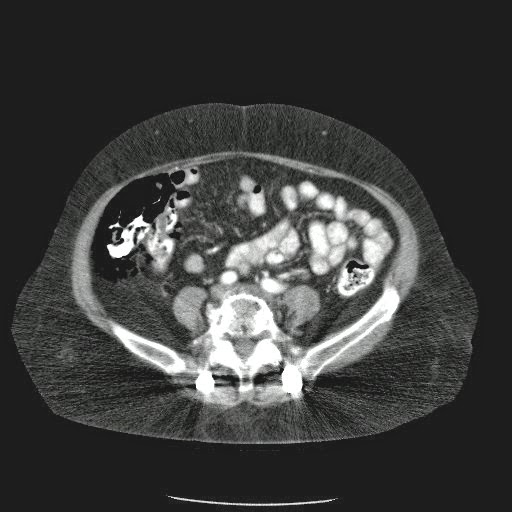

Caso Interesante #4

Adulto masculino, 1 semana de fiebre y malestar general.

¿Dónde esta ubicado el hallazgo?